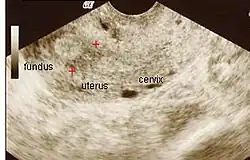

Amniotic sheet on ultrasound

The extent of adhesion formation is critical. Mild to moderate adhesions can usually be treated successfully. Extensive obliteration of the uterine cavity or fallopian tube openings (ostia) and deep endometrial or myometrial trauma may require several surgical interventions and/or hormone therapy or even be uncorrectable. If the uterine cavity is adhesion-free but the ostia remain obliterated, IVF remains an option. If the uterus has been irreparably damaged, surrogacy or adoption may be the only options.